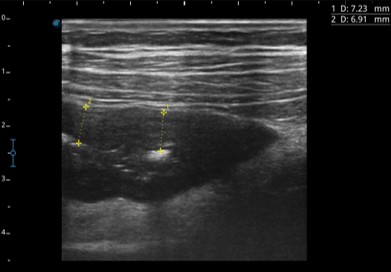

Дополнительные возможности ультразвукового исследования при воспалительных заболеваниях кишечника – эластография кишечной стенки, применение эхоконтрастных препаратов